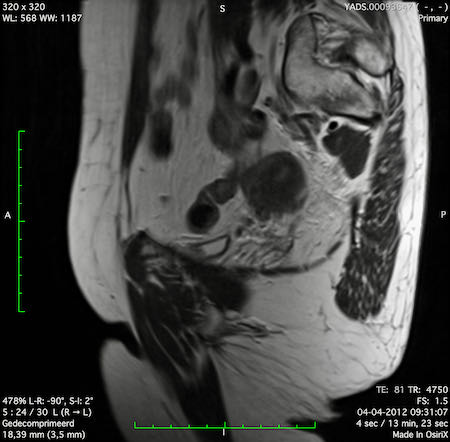

Hình ảnh

Các hình ảnh được cung cấp cho thấy ung thư biểu mô tế bào nhẫn với tình trạng dày lan tỏa thành trực tràng, hình ảnh bia bắn điển hình, và sự xâm lấn mỡ mạc treo trực tràng.